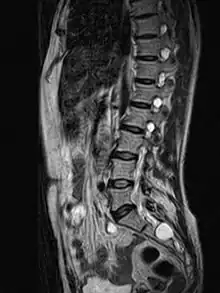

| MRI image showing a Tarlov cyst | |

MRI, or Magnetic Resonance Imaging, is considered the imaging study of choice in identifying Tarlov cysts. MRI provides better resolution of tissue density, absence of bone interference, multiplanar capabilities, and is noninvasive. Plain films may show bony erosion of the spinal canal or of the sacral foramina. On MRI pictures, the signal is the same as the CSF one.